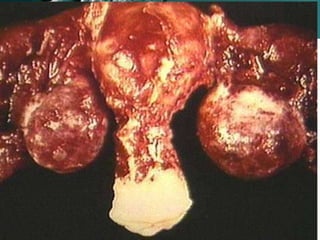

• Tubo-ovarian abscess - about 15 per cent of women

with salpingitis develop an abscess, which requires

hospitalisation.

• Tubo-ovarian abscess

– Serious sequelae of PID causing 350,000 hospitalizations and

150,000 surgeries/yr.

– Occurs in 15-30% of women requiring hospitalization for PID

treament.

– Ruptured TOA has a mortality rate as high as 9%.

– Can be diagnosed by ultrasound with 94%

sensitivity.

– Can attempt conservative management with

antibiotics but often require drainage or excision

via laparoscopy.

– 86-93% infertility rate following TOA.